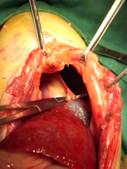

開腹時。腹腔内には、肝臓の一部、結腸、膀胱のみ。

その他の臓器は、全て胸郭内に移動している。

腹部から胸郭内をのぞいている。

本来なら横隔膜があり確認できないが、心臓が既に露出されている。

鉗子で支持している部分は、心臓と横隔膜をつないでいる靭帯である。

横隔膜と肝臓の癒着あり、注意深く分離した。

横隔膜は非常に脆弱であり、腹部の筋肉を用い横隔膜を閉鎖した。